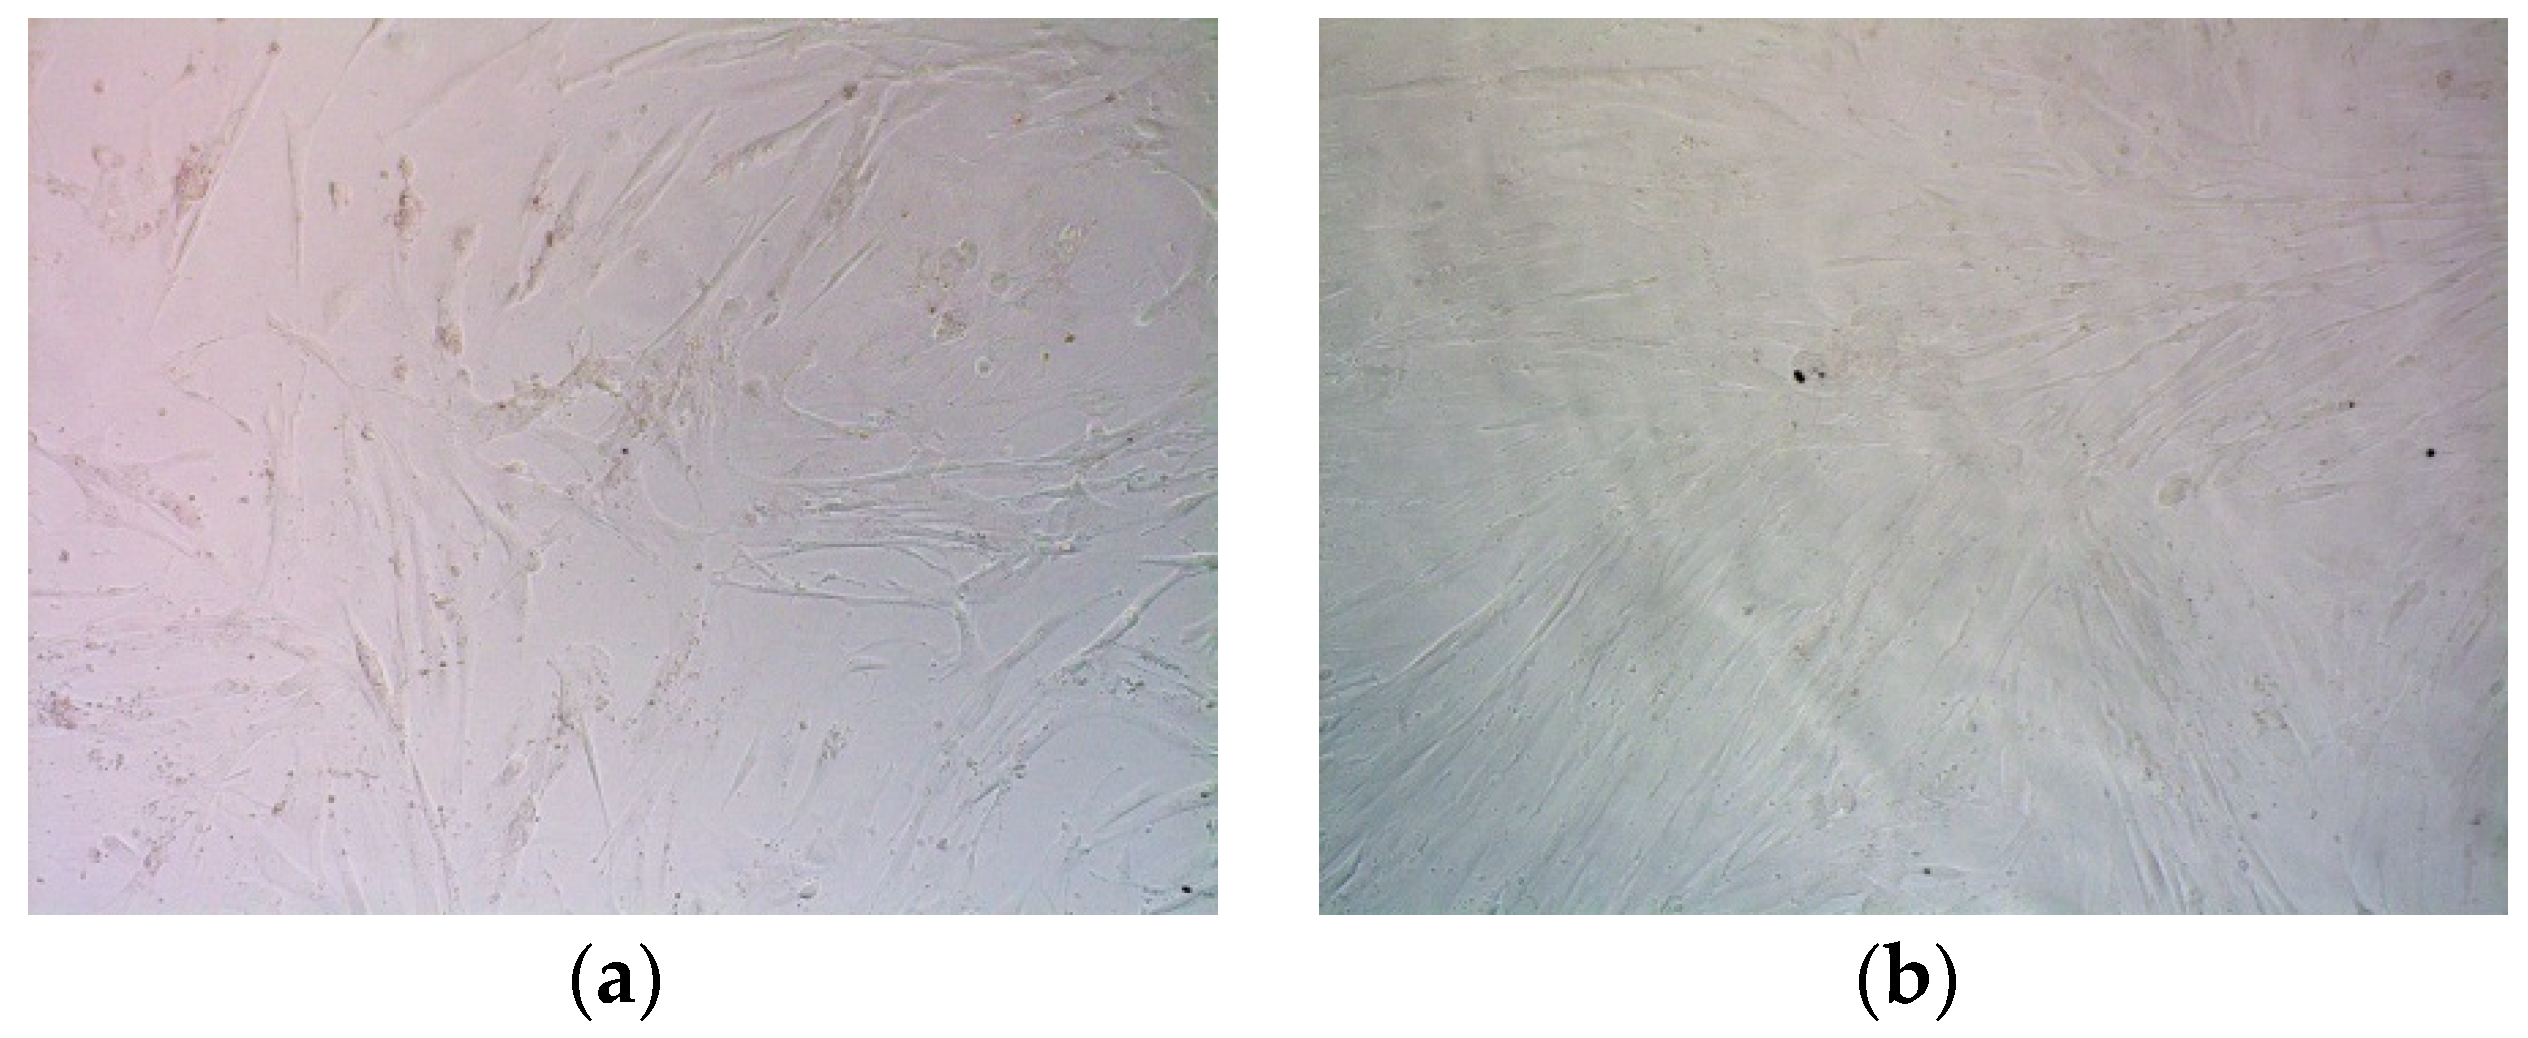

3.1. Cell Lines

- Shved, N.; Egorova, A.; Osinovskaya, N.; Kiselev, A. Development of primary monolayer cell model m odel and organotypic model of uterine leiomyoma. Methods Protoc. 2021, 41, 1–12. [Google Scholar]